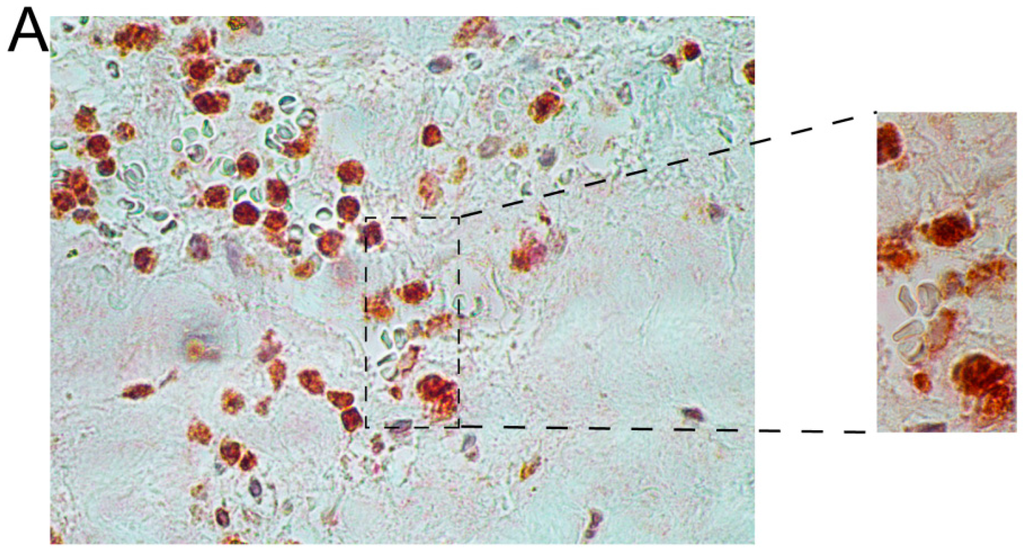

Figure 3.

Double-staining with antibodies against HCST (red) and GMZB (brown) in AAA tissue. The donors were WSU060 (A); and WSU052 (B) for the AAA tissues used in the staining shown in the upper and lower panels, respectively. See Table 1 and Table 2 for details on the aortic tissues and antibodies used, respectively, and Supplementary Figure S1 for additional images. Scale bar = 50 µm.

Immunohistochemical results with representative images of the double staining are shown in Figure 3 and Figure 4. We first used double-staining to study the co-expression of two different members of the NK pathway. These studies revealed that inflammatory cells in AAA wall were positive for both HCST (DAP10) and GRZB (Figure 3 and Supplementary Figure S1). These findings indicated that HCST (DAP10) and GZMB, both of which are enzymes and act at different steps in the NK-pathway, were actively transcribed and translated into proteins in the same cells in the AAA tissue (Figure 3 and Supplementary Figure S1).

In the current study, the immunostaining of selected members in the NK-pathway confirmed the mRNA expression results on the protein level (Figure 2). The histological investigation suggested NK cells were not the only cell type involved in the activation of the NK pathway because most inflammatory cells showed positive staining (Figure 2). A double staining with GZMB and HCST demonstrated that products of the beginning of the activation pathway and the final products were produced in the same cell, providing evidence for the complete activation of the pathway (Figure 3 and Supplementary Figure S1).